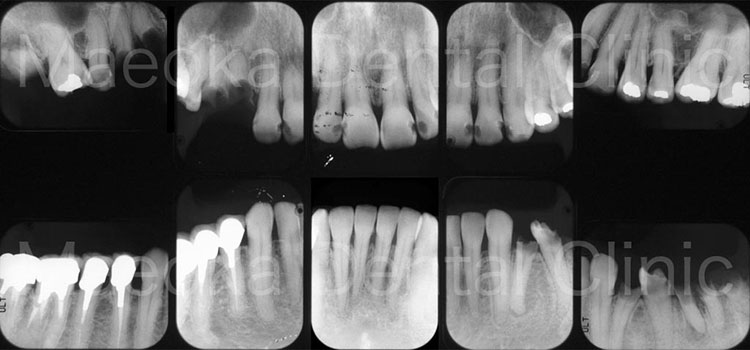

患者さんは49歳女性の方で、「全体的にしっかりと治したい」という主訴で来院されました。

出産を機にお口の環境が悪くなっていったとのことでしたが、勇気が出せずになかなか歯科を受診できなかったそうです。

診査を行うと奥歯の噛み合わせが失われており、審美面、機能面ともに大掛かりな介入が必要な状態でした。

はじめに患者さんから伺った情報を基に、現在の環境になってしまった根本的な原因を模索し、原因除去を行っていきました。その後、歯の移植(右下5を右上3に移植)、部分的な矯正などを行った上で審美的な範囲はセラミックスを用いた被せ物、歯の削除量を最小限にするために見えない箇所は金属を用いた被せ物で最終的な修復を行いました(一部表面的な虫歯は残っていますが、患者さんと相談した上で、今の段階で積極的に削ることは避け、経過観察を行うこととしています)。

プロビジョナルレストレーション(精密な仮歯)を入れた上で機能上問題ないことを確認するなどチェック期間にも時間を要したため、5年に及ぶ治療期間を要しましたが、残りの患者さんの人生の長さを考えると必要十分な治療であったと考えます。

保存不可能と思われる歯が多数ある中ではありましたが、結果として抜歯に至った歯は3本のみで、インプラントを用いることなく、患者さん自身の歯でお口の環境を再構築することができました。

今後はメインテナンスで治療終了時の環境を長期的に維持できるように努めていきます。

治療前(10枚法)

治療後(10枚法)